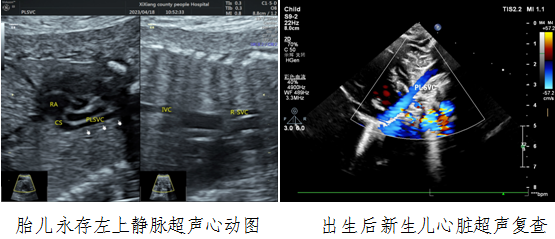

病例一,30岁,孕22w+,G2P1,既往产检未见胎儿心脏结构异常。2023年4月到西乡县医院例行常规产前超声检查,六合彩网站

对口帮扶贾玄慧医生,超声发现胎儿存在先天大血管发育异常——永存左上腔静脉,指导孕妇进行产前咨询及产后随访。胎儿出生后1天,贾玄慧医生立即对该新生儿进行了心脏复查,结果确诊永存左上腔静脉诊断明确。